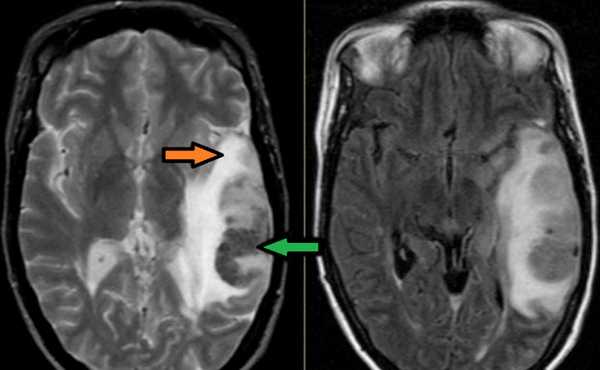

Тромбоз правого поперечного синуса - гипоинтенсивные участки по Т2 (внутриклеточный дезоксигемоглобин).

Для подтверждения тромбоза венозного синуса и определения точной локализации и протяженности тромба необходимо проведение МР-венографии.

МР-венография - отсутствие визуализации кровотока в правом поперечном синусе и яремной вене.

МРТ головного мозга: справа (зеленая стрелка) на Т2-взвешенном изображении отмечается имеющийся в норме феномен «пустоты потока» от правого сигмовидного синуса и яремной Вены. Слева (оранжевая стрелка) отмечается аномально высокий сигнал, в результате, вероятнее, тромбоза. Для подтверждения синус-тромбоза и окончательного определения локализации и протяженности тромбоза необходимо проведение МР-венографии.

МР-венография: тромбоз левого поперечного синуса. Отмечается потеря МР-сигнала от левого поперечного синуса.

Наличие визуализации синуса на «сырых» данных или же МРТ головного мозга подтверждает тромбоз синуса и исключает его гипоплазию.

МР-венография: тромбоз правого поперечного синуса. Отмечается потеря МР-сигнала от правого поперечного синуса.

Наличие визуализации синуса на «сырых» данных или же МРТ головного мозга подтверждает тромбоз синуса и исключает его гипо- и аплазию.

Тромбоз правого поперечного синуса. Отсутствие феномена «пустоты потока» от правого поперечного синуса на МРТ головного мозга. Отсутствие визуализации правого поперечного синуса на МР-венографии.

Как указывалось выше, в случаях возникновения клинической картины церебрального венозного тромбоза по ходу вен и синусов на МРТ головного мозга в части случаев обнаруживается зона ишемии и геморрагии.

МРТ головного мозга: отмечается сочетание вазогенного (оранжевая стрелка), цитотоксического отека и кровоизлияния (зеленая стрелка). Данная МР-картина, а также расположение патологической зоны в проекции височной доли, заставляет задуматься о геморрагическом венозном НМК вследствие тромбоза вены Лаббе. Для подтверждения необходимо проведение МР-венографии или МРТ с контрастным усилением.